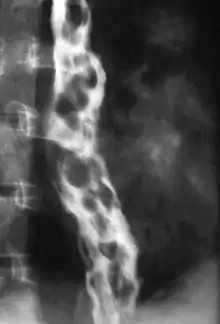

Varice œsophagienne

Le diagnostic se fait par endoscopie digestive haute, on retrouve un aspect de cordons bleuâtres, saillants, au niveau de la partie inférieure de l’œsophage.